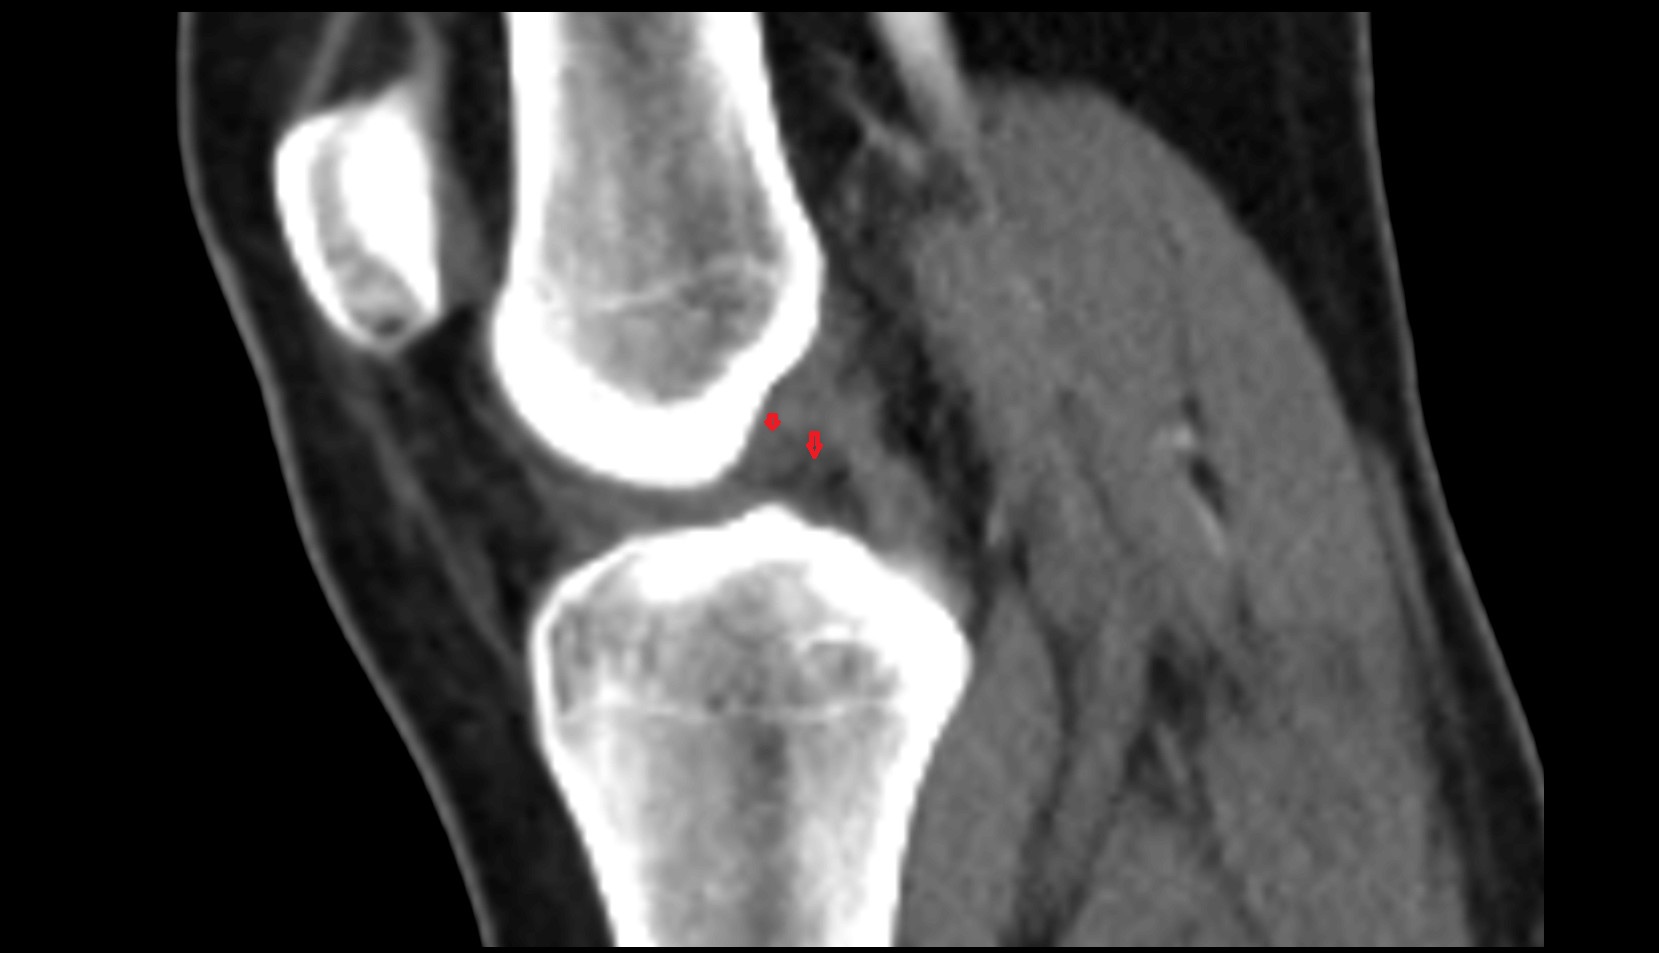

- Knee Joint